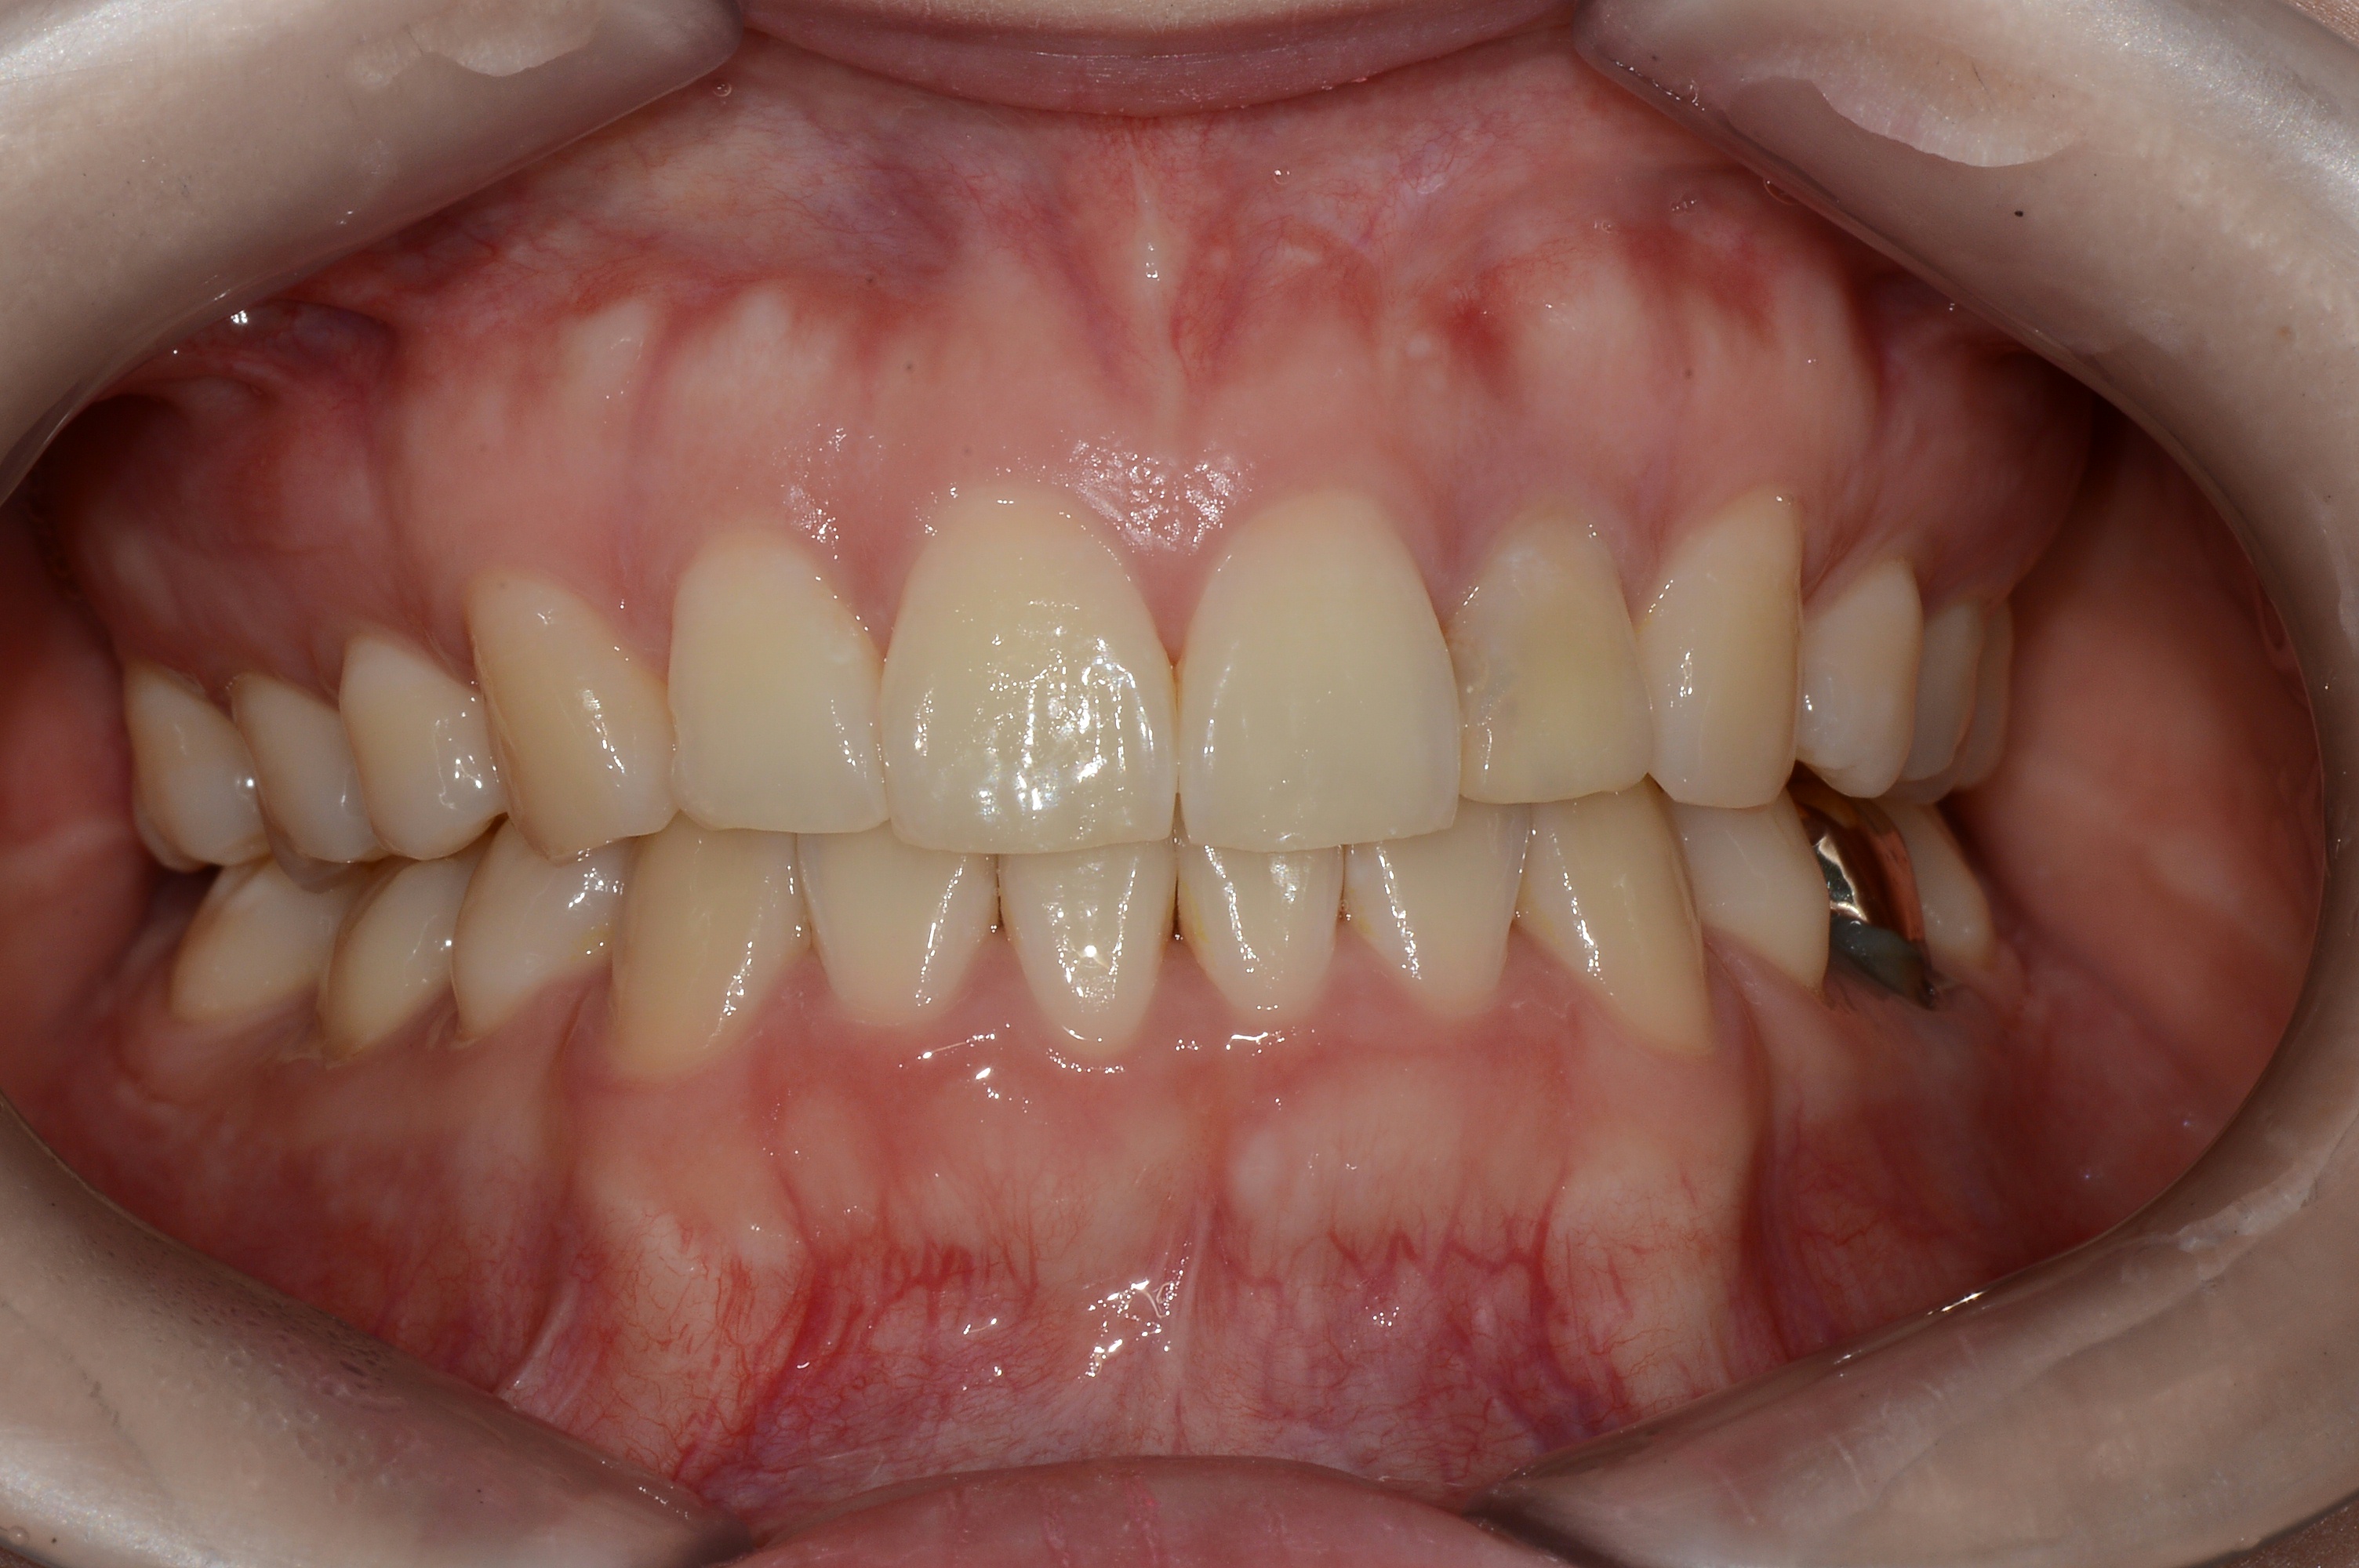

치료 전 사진입니다.